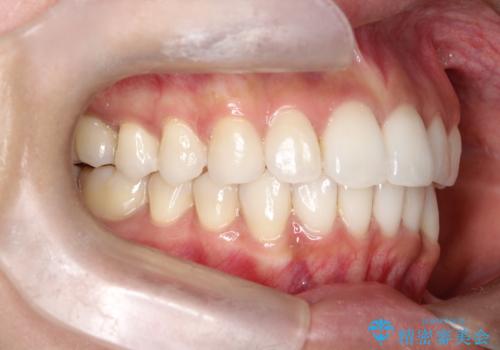

前歯のがたつきをマウスピース矯正で改善。IPRと遠心移動による非抜歯インビザライン治療

精密検査の結果、歯を並べるためのスペースが不足していましたが、抜歯をせずに改善したいというご希望があったため、IPR(歯の側面をわずかに削る処置)と、奥歯を後ろに動かす「遠心移動」を組み合わせる計画を立案。透明なマウスピース装置であるインビザラインを使用し、無理のない範囲でスペースを確保しながら歯列を整えることとしました。

治療では、マウスピースの設計に基づき、奥歯から順に後ろへ移動させる遠心移動を行い、前歯のためのスペースを作りました。同時に、数箇所の歯の間にIPRを施すことで、歯の健康に影響のない範囲で精密に隙間を確保しました。

1年半の治療期間を経て、重なり合っていた前歯はスムーズに整列し、理想的なアーチ状の歯並びへと改善されました。抜歯を行わずに治療を完了したことで、噛み合わせのバランスを維持しながら、審美性を大きく向上させることができました。現在は保定期間に入り、美しい状態を維持されています。